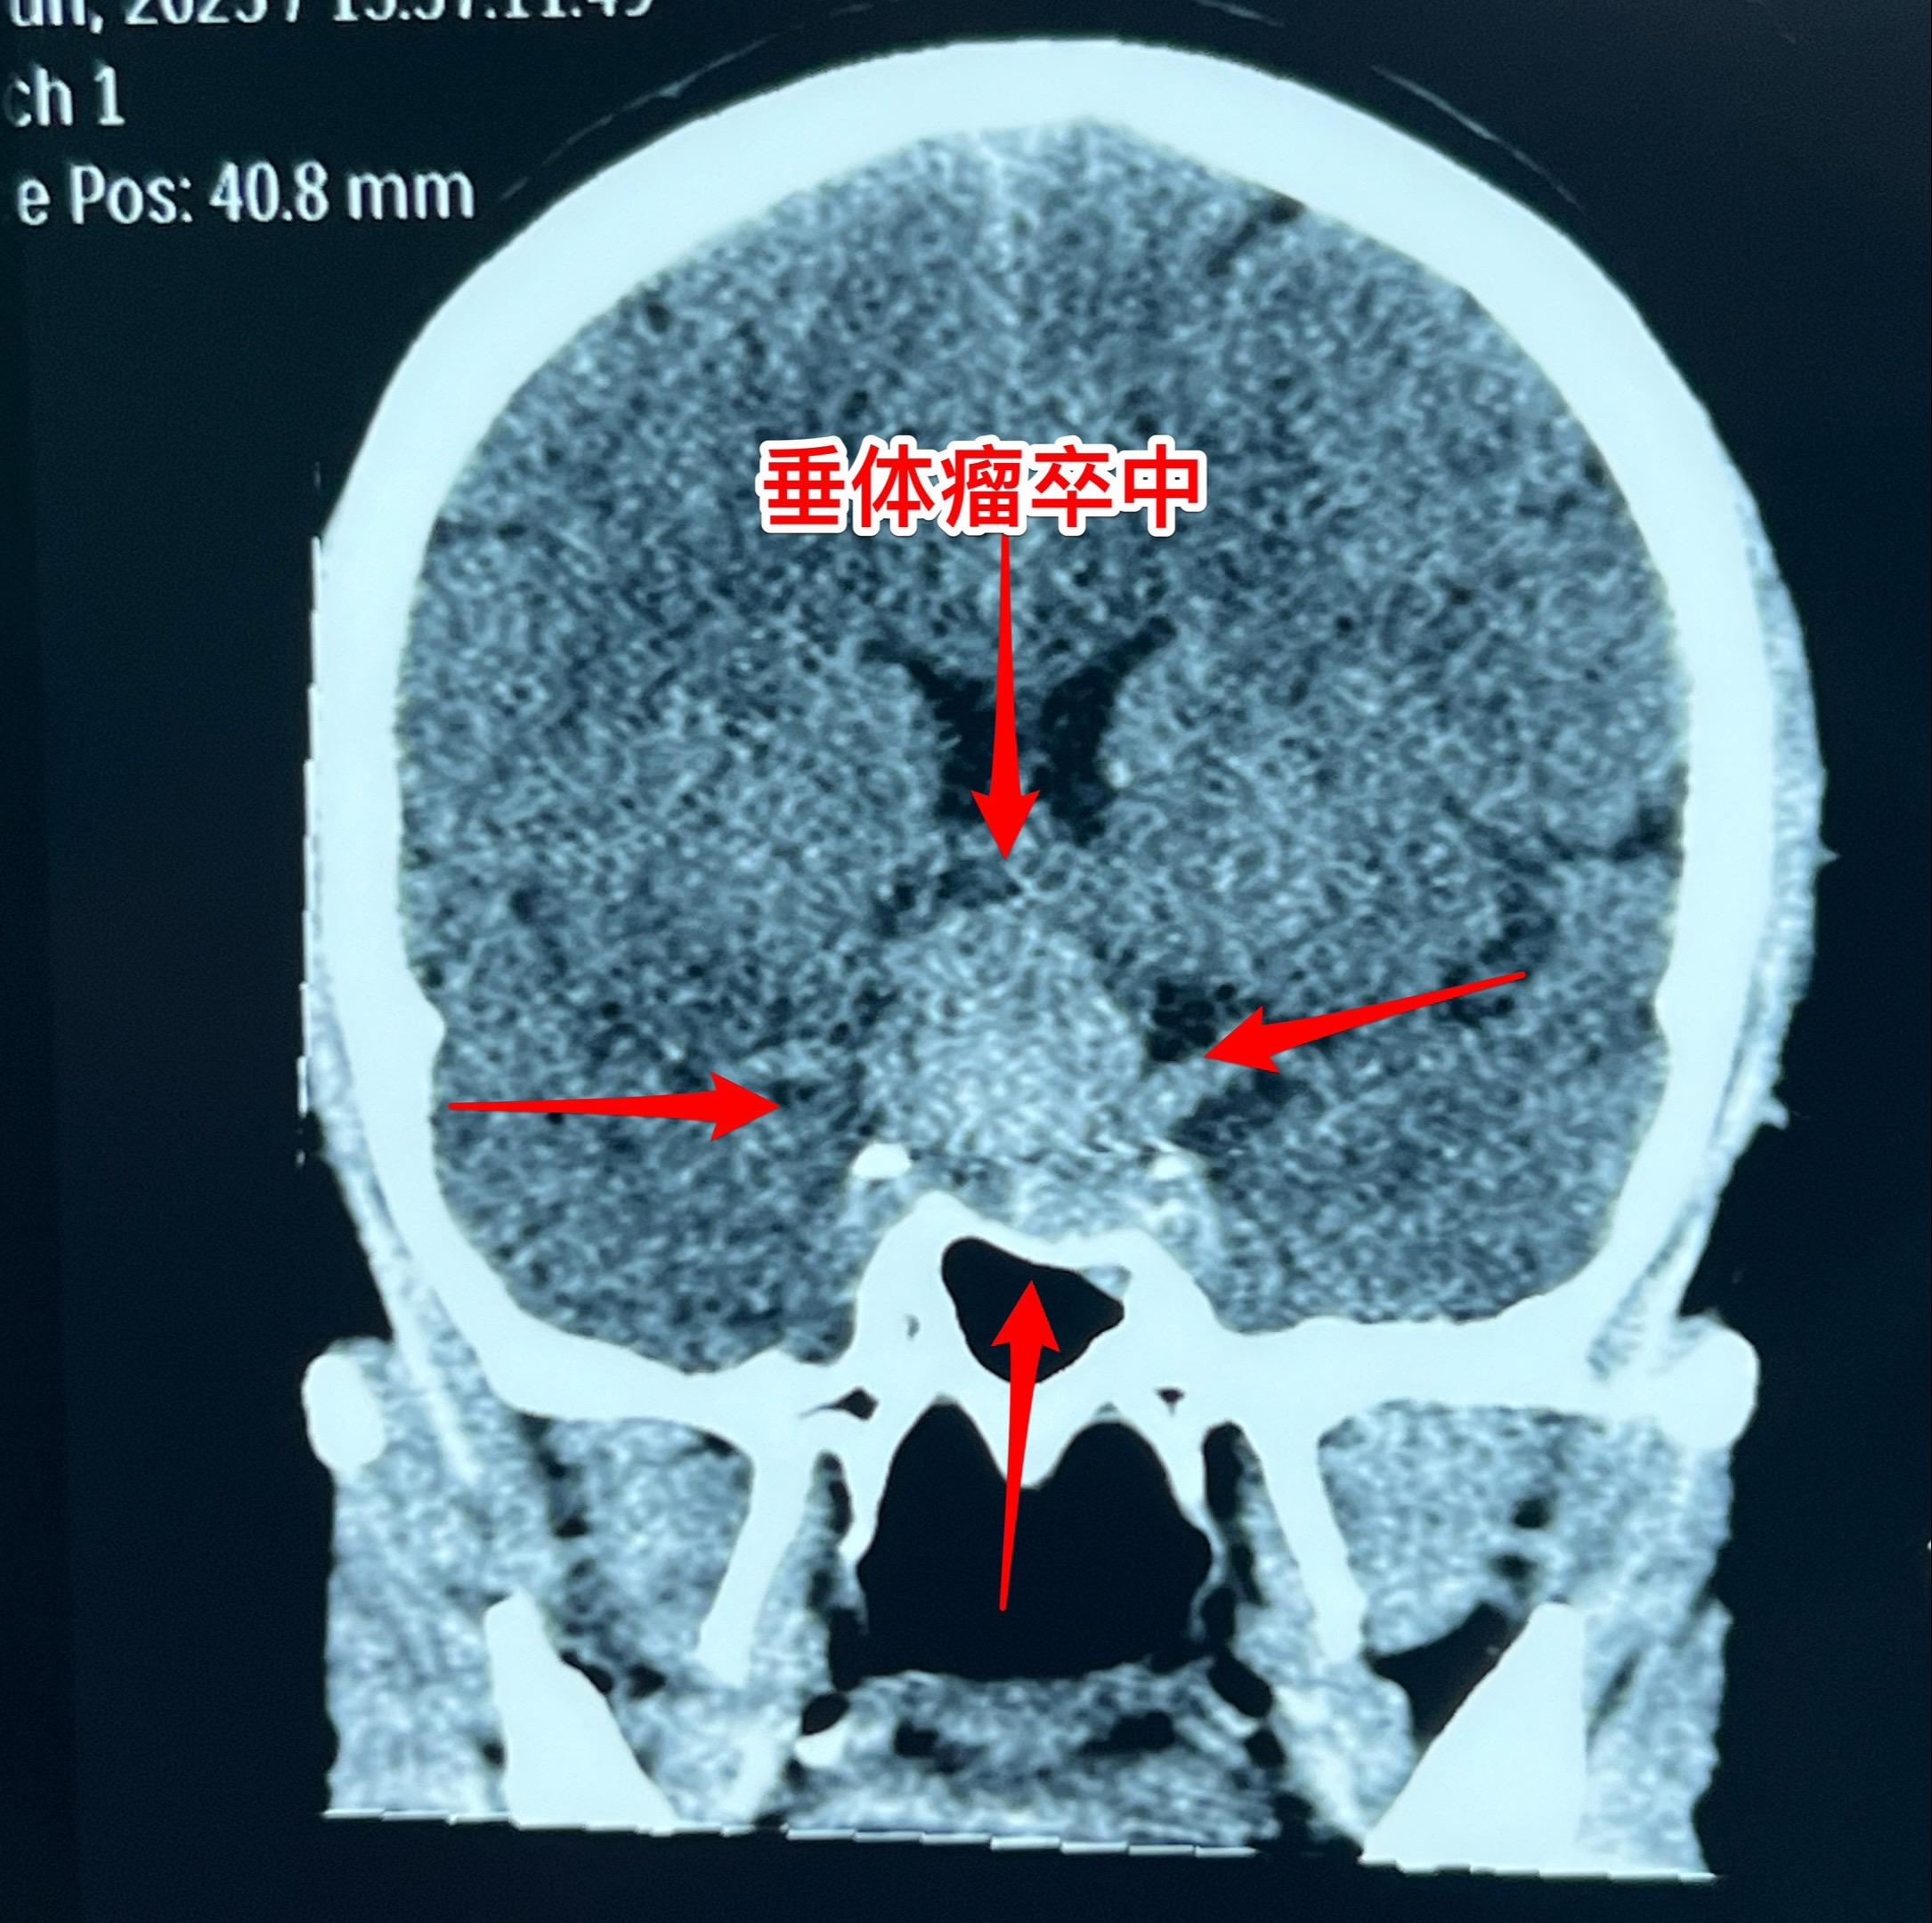

两个月内两个垂体瘤卒中 病例 垂体瘤卒中的最明显的症状是突发视力下降,可以伴有头痛。病人到医院眼科就诊一般找不出眼科的疾病,这时候只要作一个头部CT或者磁共振即可确诊垂体瘤卒中。一旦确诊,则应该尽快行手术切除垂体瘤,对视神经进行减压,争取挽救视力。 图1-6:男性,21岁,入院前六天突发视力下降,几乎双眼失明。在当地医院曾经怀疑是颅咽管瘤。在我科住院后给予激素治疗、对症治疗后视力呈现好转趋势。化验结果显示垂体功能低下(甲状腺激素低下、肾上腺皮质功能低下、性激素低下)。7月3日经鼻手术切除垂体